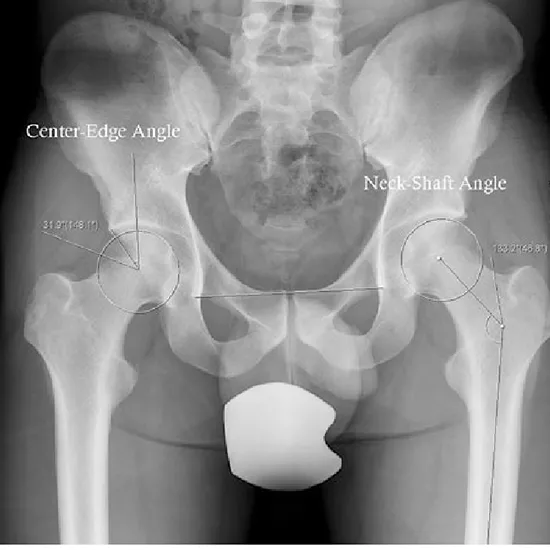

An X-ray of the pelvis is used to see the hip bones, the top part of the thigh bone (called the proximal femur), the hip joint, and the skin and muscles.

• This view is useful in assessing:

• Joint Dislocations

• Fractures

• Trauma

• Bone lesion

• Degenerative disease.

• Femoro-acetabular impingement (FAI)

• Hip dysplasia

• Acetabulum fracture